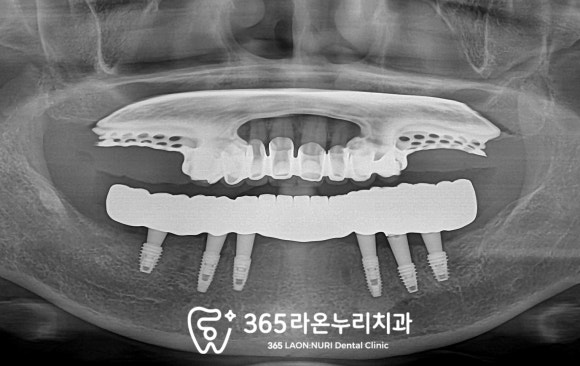

파노라마 엑스레이를 찍어

조금 더 자세히 살펴봤는데요,

부러진 치근 끝에 일부 염증 소견도 보이니

하루빨리 문제 해결이 필요할 것 같네요.

다시 본론으로 돌아와

하치조신경을 고려하고

치조골의 두께 및 초기고정력에 유리한 곳에

총 6개의 픽스처를 심었습니다.